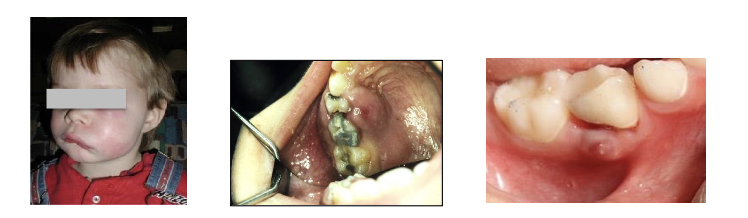

Osteomyelitis clinical presentation

A

Here’s an acronym for the description you provided:

“FIRE” to the bones

F: Fever – A common symptom of the infection, signaling the body’s response to the illness.

I: Infection – The underlying cause of pain, swelling, and the radiographic “moth-eaten” appearance in bone.

R: Radiographic Changes – The “moth-eaten” appearance on X-rays indicating severe bone involvement.

E: Edema (Swelling) – Swelling is another prominent symptom that accompanies the infection.